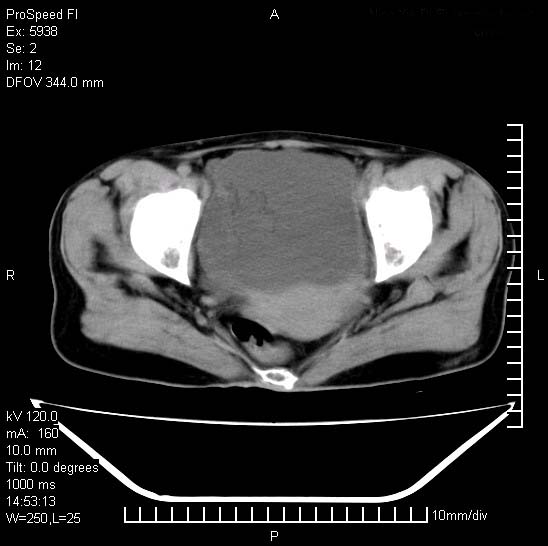

反复小腹疼痛,盆腔积液3年,无发热,曾抗痨一段时间。

右下腹肠管壁增厚,边缘有侵润改变及点状低密度影,内侧可见局限性肿块。考虑-----淋巴瘤或增生型肠结核----盆腔积液-----建议肠镜检查

考虑盆腔及右下腹感染性病变(结核可能)。

结核性腹膜炎伴积液。右侧髂骨骨窗看看,是否有骨质破坏。

提示结核性腹膜炎合并盆腔积液。建议查ppd或tb抗体。

考虑右下腹及盆腔感染性病变(结核?)。